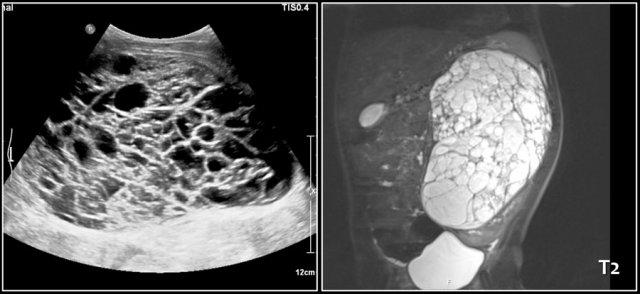

Bé trai một tuổi nhập viện vì bụng phình to.

Siêu âm phát hiện một tổn thương dạng nang kích thước lớn, trải dài từ gan xuống vùng chậu.

Ghi nhận có một số cặn lắng bên trong.

Ảnh MRI mặt phẳng coronal chuỗi xung T2W cho thấy rõ hơn mức độ lan rộng của tổn thương.

Trong phẫu thuật, tổn thương được xác định bám vào đại tràng lên, đại tràng này đã được cắt bỏ cùng với u nang bạch huyết.

Đây là trường hợp bé trai hai tuổi với triệu chứng nôn ra mật.

Siêu âm cho thấy một khối u đa nang thành mỏng kích thước lớn, có tính chất khá mềm.

Trong phẫu thuật, u nang bạch huyết của mạc treo ruột đã được cắt bỏ.